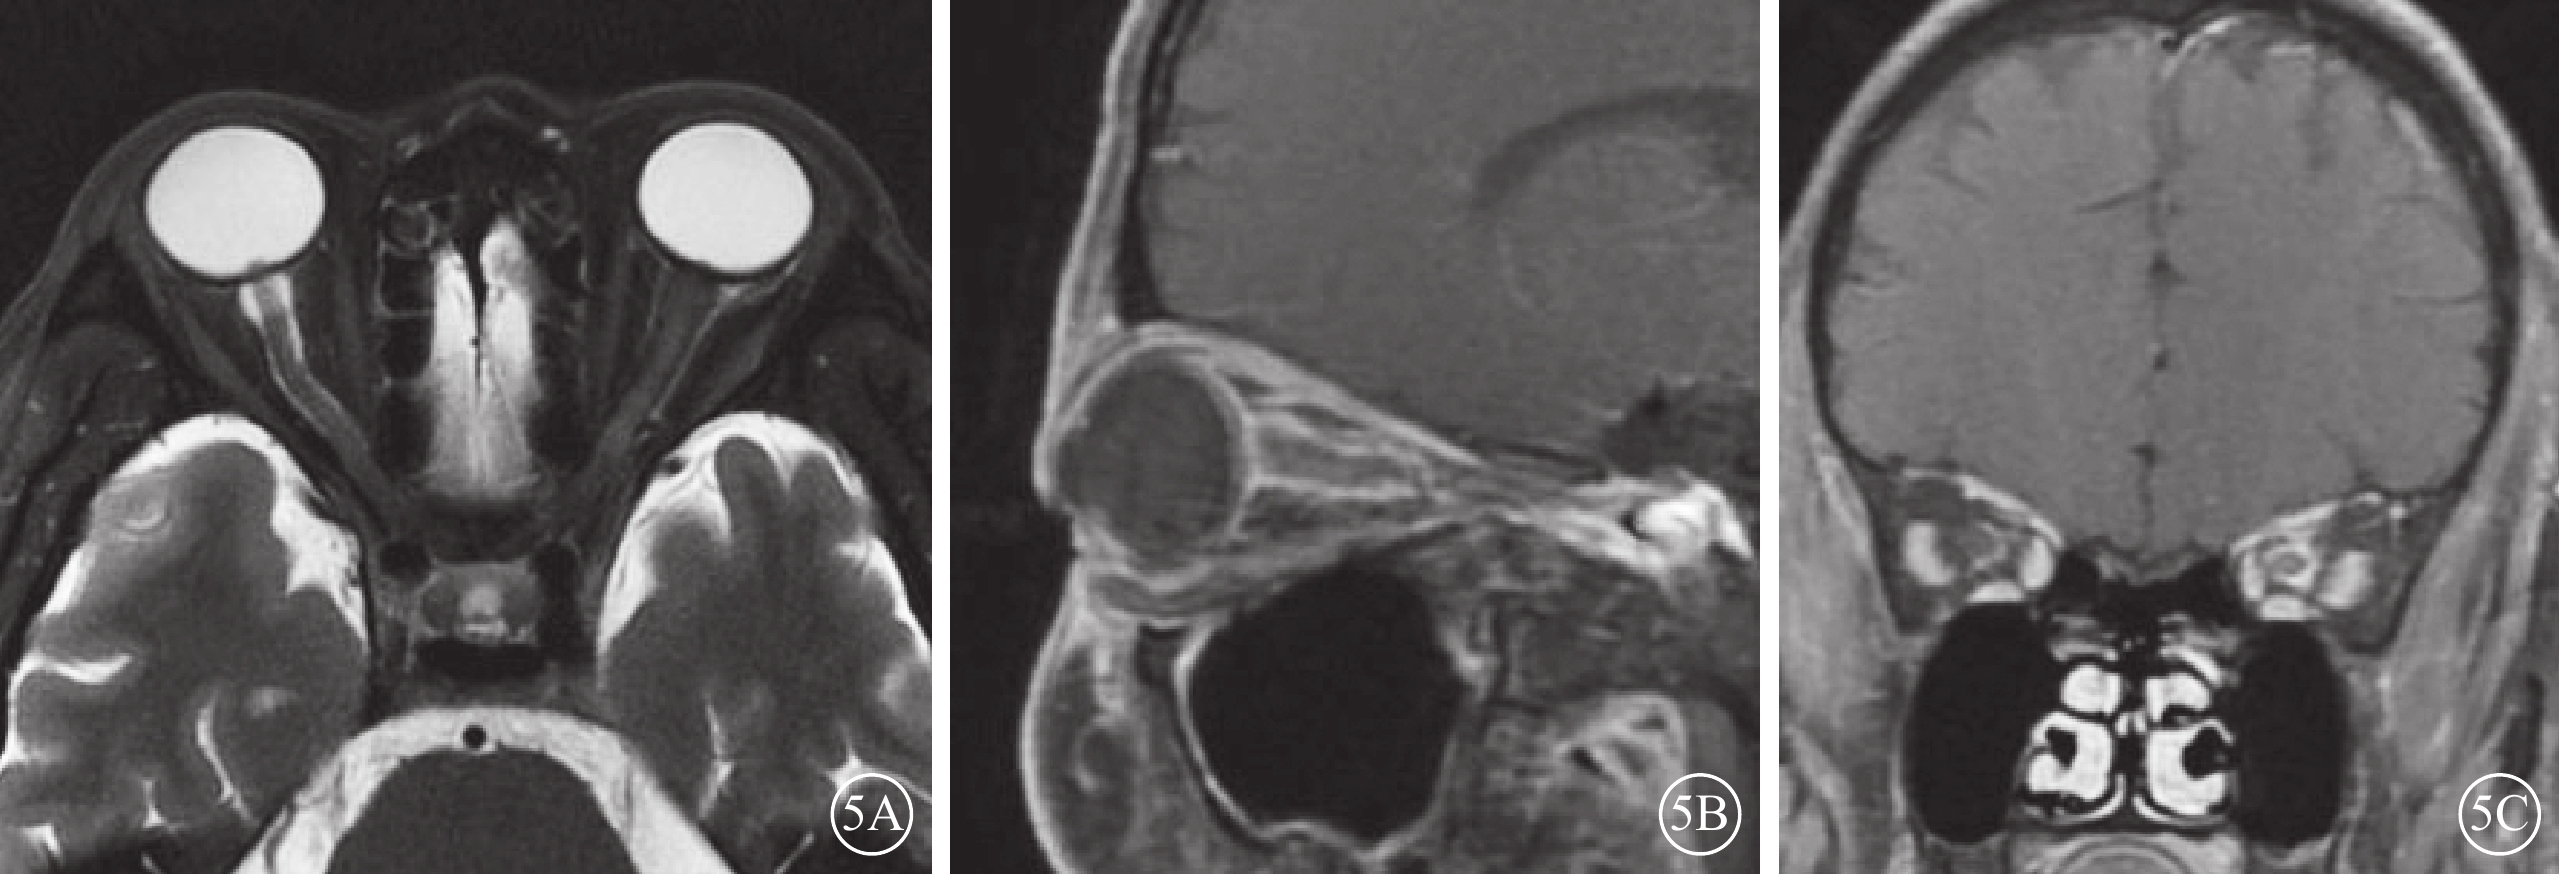

ION患眼,T2加權像視神經彌漫性或局限性增粗,伴或不伴鞘膜間隙增寬;T1加權像造影劑增強序列可見視神經鞘膜強化,其中軸位像示視神經呈雙軌樣強化(雙軌征),冠狀位像示視神經呈環形強化(袖套征),但視神經實質無明顯增粗或強化(圖5)。其中,繼發于全身性惡性腫瘤的13例17只眼中,合并眼外肌等眶內軟組織浸潤改變1例1只眼;繼發于眼眶周圍惡性腫瘤的7例9只眼,均可見與眶周原發性惡性腫瘤相延續、且累及視神經的軟組織腫物(圖6)。合并癌性腦膜炎的4例6只眼,均可見腦膜局灶性或彌漫性增厚和強化;合并顱內轉移灶的4例4只眼,均可見腦實質內散在分布的點狀或灶狀長T2信號病灶伴強化。